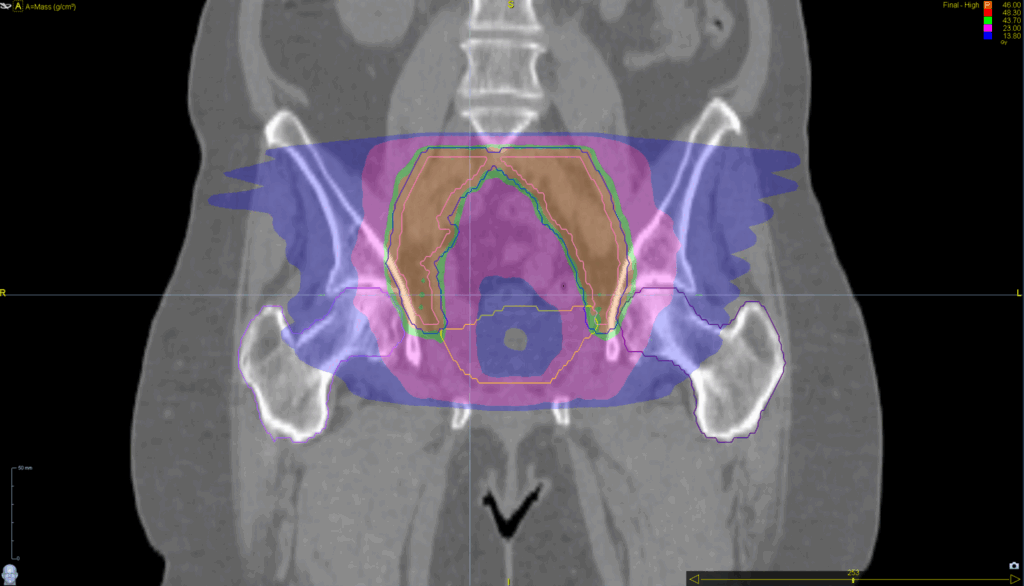

Treatment Plan Images

Fractionation / Protocol Used

46 Gy in 23 fractions

PTV(s) Volume, Length

545 cc, 15 cm